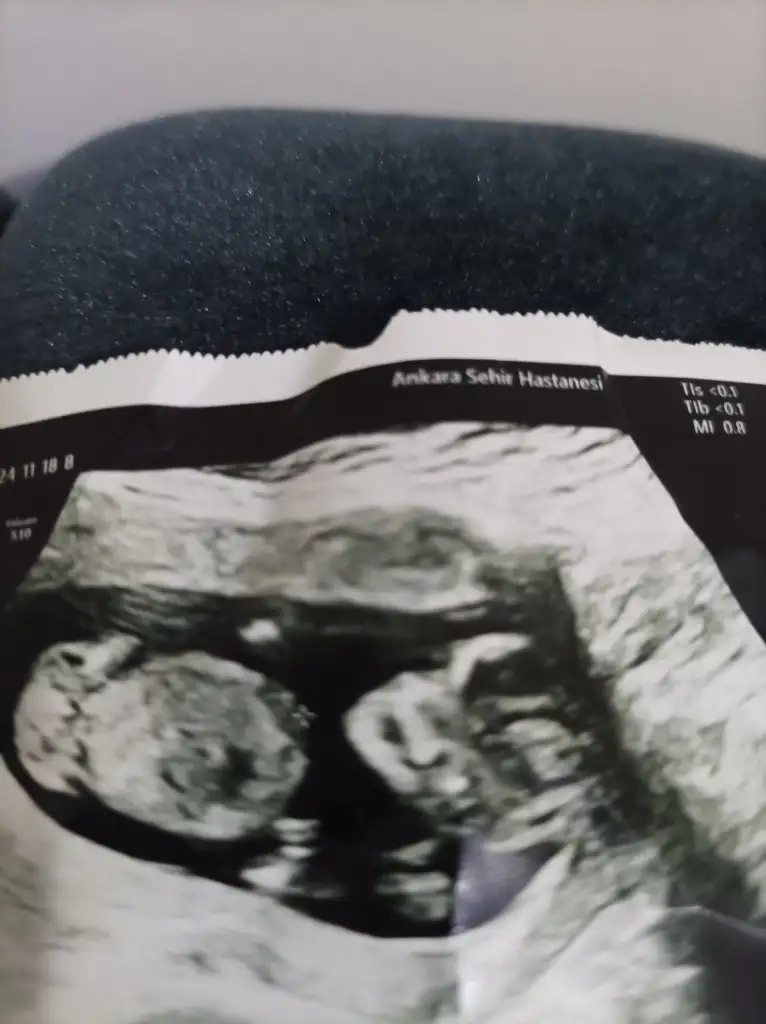

• IMG_20241118_232856.webp

IMG_20241118_232856.webp

24,1 KB · Görüntüleme: 56

• IMG_20241118_230009.webp

IMG_20241118_230009.webp

23,9 KB · Görüntüleme: 49